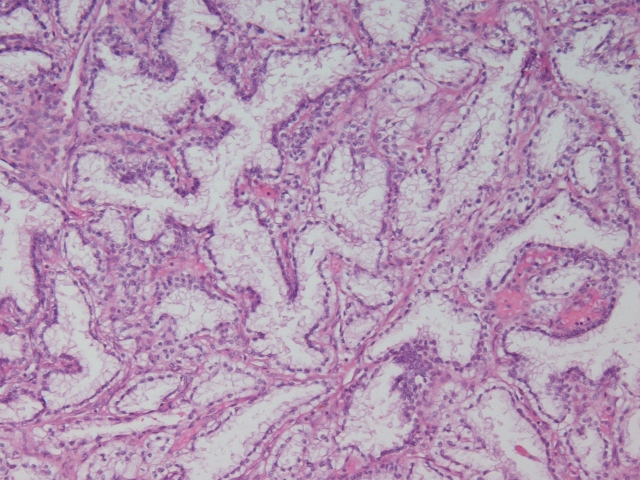

Classification of renal tumors

Case ID: 963

21 Jan, 2016